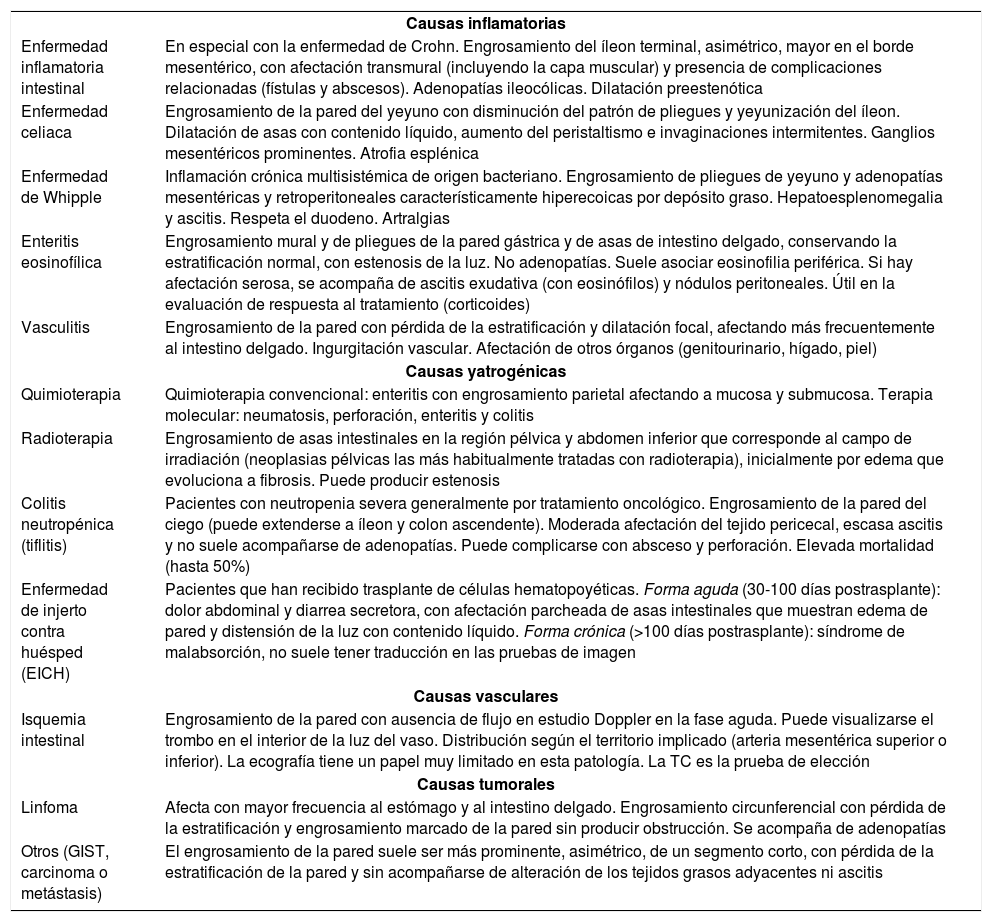

Intestino delgado distalLas infecciones del íleon terminal con frecuencia pueden extenderse al ciego (fig. 2). El principal diagnóstico diferencial es la enfermedad inflamatoria intestinal, en etapas precoces habitualmente indistinguible (tabla 2).

Diagnóstico diferencial de las enterocolitis infecciosas. Otras causas de afectación intestinal difusa

| Causas inflamatorias | |

| Enfermedad inflamatoria intestinal | En especial con la enfermedad de Crohn. Engrosamiento del íleon terminal, asimétrico, mayor en el borde mesentérico, con afectación transmural (incluyendo la capa muscular) y presencia de complicaciones relacionadas (fístulas y abscesos). Adenopatías ileocólicas. Dilatación preestenótica |

| Enfermedad celiaca | Engrosamiento de la pared del yeyuno con disminución del patrón de pliegues y yeyunización del íleon. Dilatación de asas con contenido líquido, aumento del peristaltismo e invaginaciones intermitentes. Ganglios mesentéricos prominentes. Atrofia esplénica |

| Enfermedad de Whipple | Inflamación crónica multisistémica de origen bacteriano. Engrosamiento de pliegues de yeyuno y adenopatías mesentéricas y retroperitoneales característicamente hiperecoicas por depósito graso. Hepatoesplenomegalia y ascitis. Respeta el duodeno. Artralgias |

| Enteritis eosinofílica | Engrosamiento mural y de pliegues de la pared gástrica y de asas de intestino delgado, conservando la estratificación normal, con estenosis de la luz. No adenopatías. Suele asociar eosinofilia periférica. Si hay afectación serosa, se acompaña de ascitis exudativa (con eosinófilos) y nódulos peritoneales. Útil en la evaluación de respuesta al tratamiento (corticoides) |

| Vasculitis | Engrosamiento de la pared con pérdida de la estratificación y dilatación focal, afectando más frecuentemente al intestino delgado. Ingurgitación vascular. Afectación de otros órganos (genitourinario, hígado, piel) |

| Causas yatrogénicas | |

| Quimioterapia | Quimioterapia convencional: enteritis con engrosamiento parietal afectando a mucosa y submucosa. Terapia molecular: neumatosis, perforación, enteritis y colitis |

| Radioterapia | Engrosamiento de asas intestinales en la región pélvica y abdomen inferior que corresponde al campo de irradiación (neoplasias pélvicas las más habitualmente tratadas con radioterapia), inicialmente por edema que evoluciona a fibrosis. Puede producir estenosis |

| Colitis neutropénica (tiflitis) | Pacientes con neutropenia severa generalmente por tratamiento oncológico. Engrosamiento de la pared del ciego (puede extenderse a íleon y colon ascendente). Moderada afectación del tejido pericecal, escasa ascitis y no suele acompañarse de adenopatías. Puede complicarse con absceso y perforación. Elevada mortalidad (hasta 50%) |

| Enfermedad de injerto contra huésped (EICH) | Pacientes que han recibido trasplante de células hematopoyéticas. Forma aguda (30-100 días postrasplante): dolor abdominal y diarrea secretora, con afectación parcheada de asas intestinales que muestran edema de pared y distensión de la luz con contenido líquido. Forma crónica (>100 días postrasplante): síndrome de malabsorción, no suele tener traducción en las pruebas de imagen |

| Causas vasculares | |

| Isquemia intestinal | Engrosamiento de la pared con ausencia de flujo en estudio Doppler en la fase aguda. Puede visualizarse el trombo en el interior de la luz del vaso. Distribución según el territorio implicado (arteria mesentérica superior o inferior). La ecografía tiene un papel muy limitado en esta patología. La TC es la prueba de elección |

| Causas tumorales | |

| Linfoma | Afecta con mayor frecuencia al estómago y al intestino delgado. Engrosamiento circunferencial con pérdida de la estratificación y engrosamiento marcado de la pared sin producir obstrucción. Se acompaña de adenopatías |

| Otros (GIST, carcinoma o metástasis) | El engrosamiento de la pared suele ser más prominente, asimétrico, de un segmento corto, con pérdida de la estratificación de la pared y sin acompañarse de alteración de los tejidos grasos adyacentes ni ascitis |

El diagnóstico diferencial de las infecciones intestinales incluye otros cuadros de abdomen agudo de origen intestinal (apendicitis, diverticulitis, adenitis, etc.), ya tratados en otro artículo de esta serie, y especialmente, otras causas de afectación intestinal difusa de naturaleza inflamatoria, yatrogénica, vascular o tumoral (tabla 2)28–31.